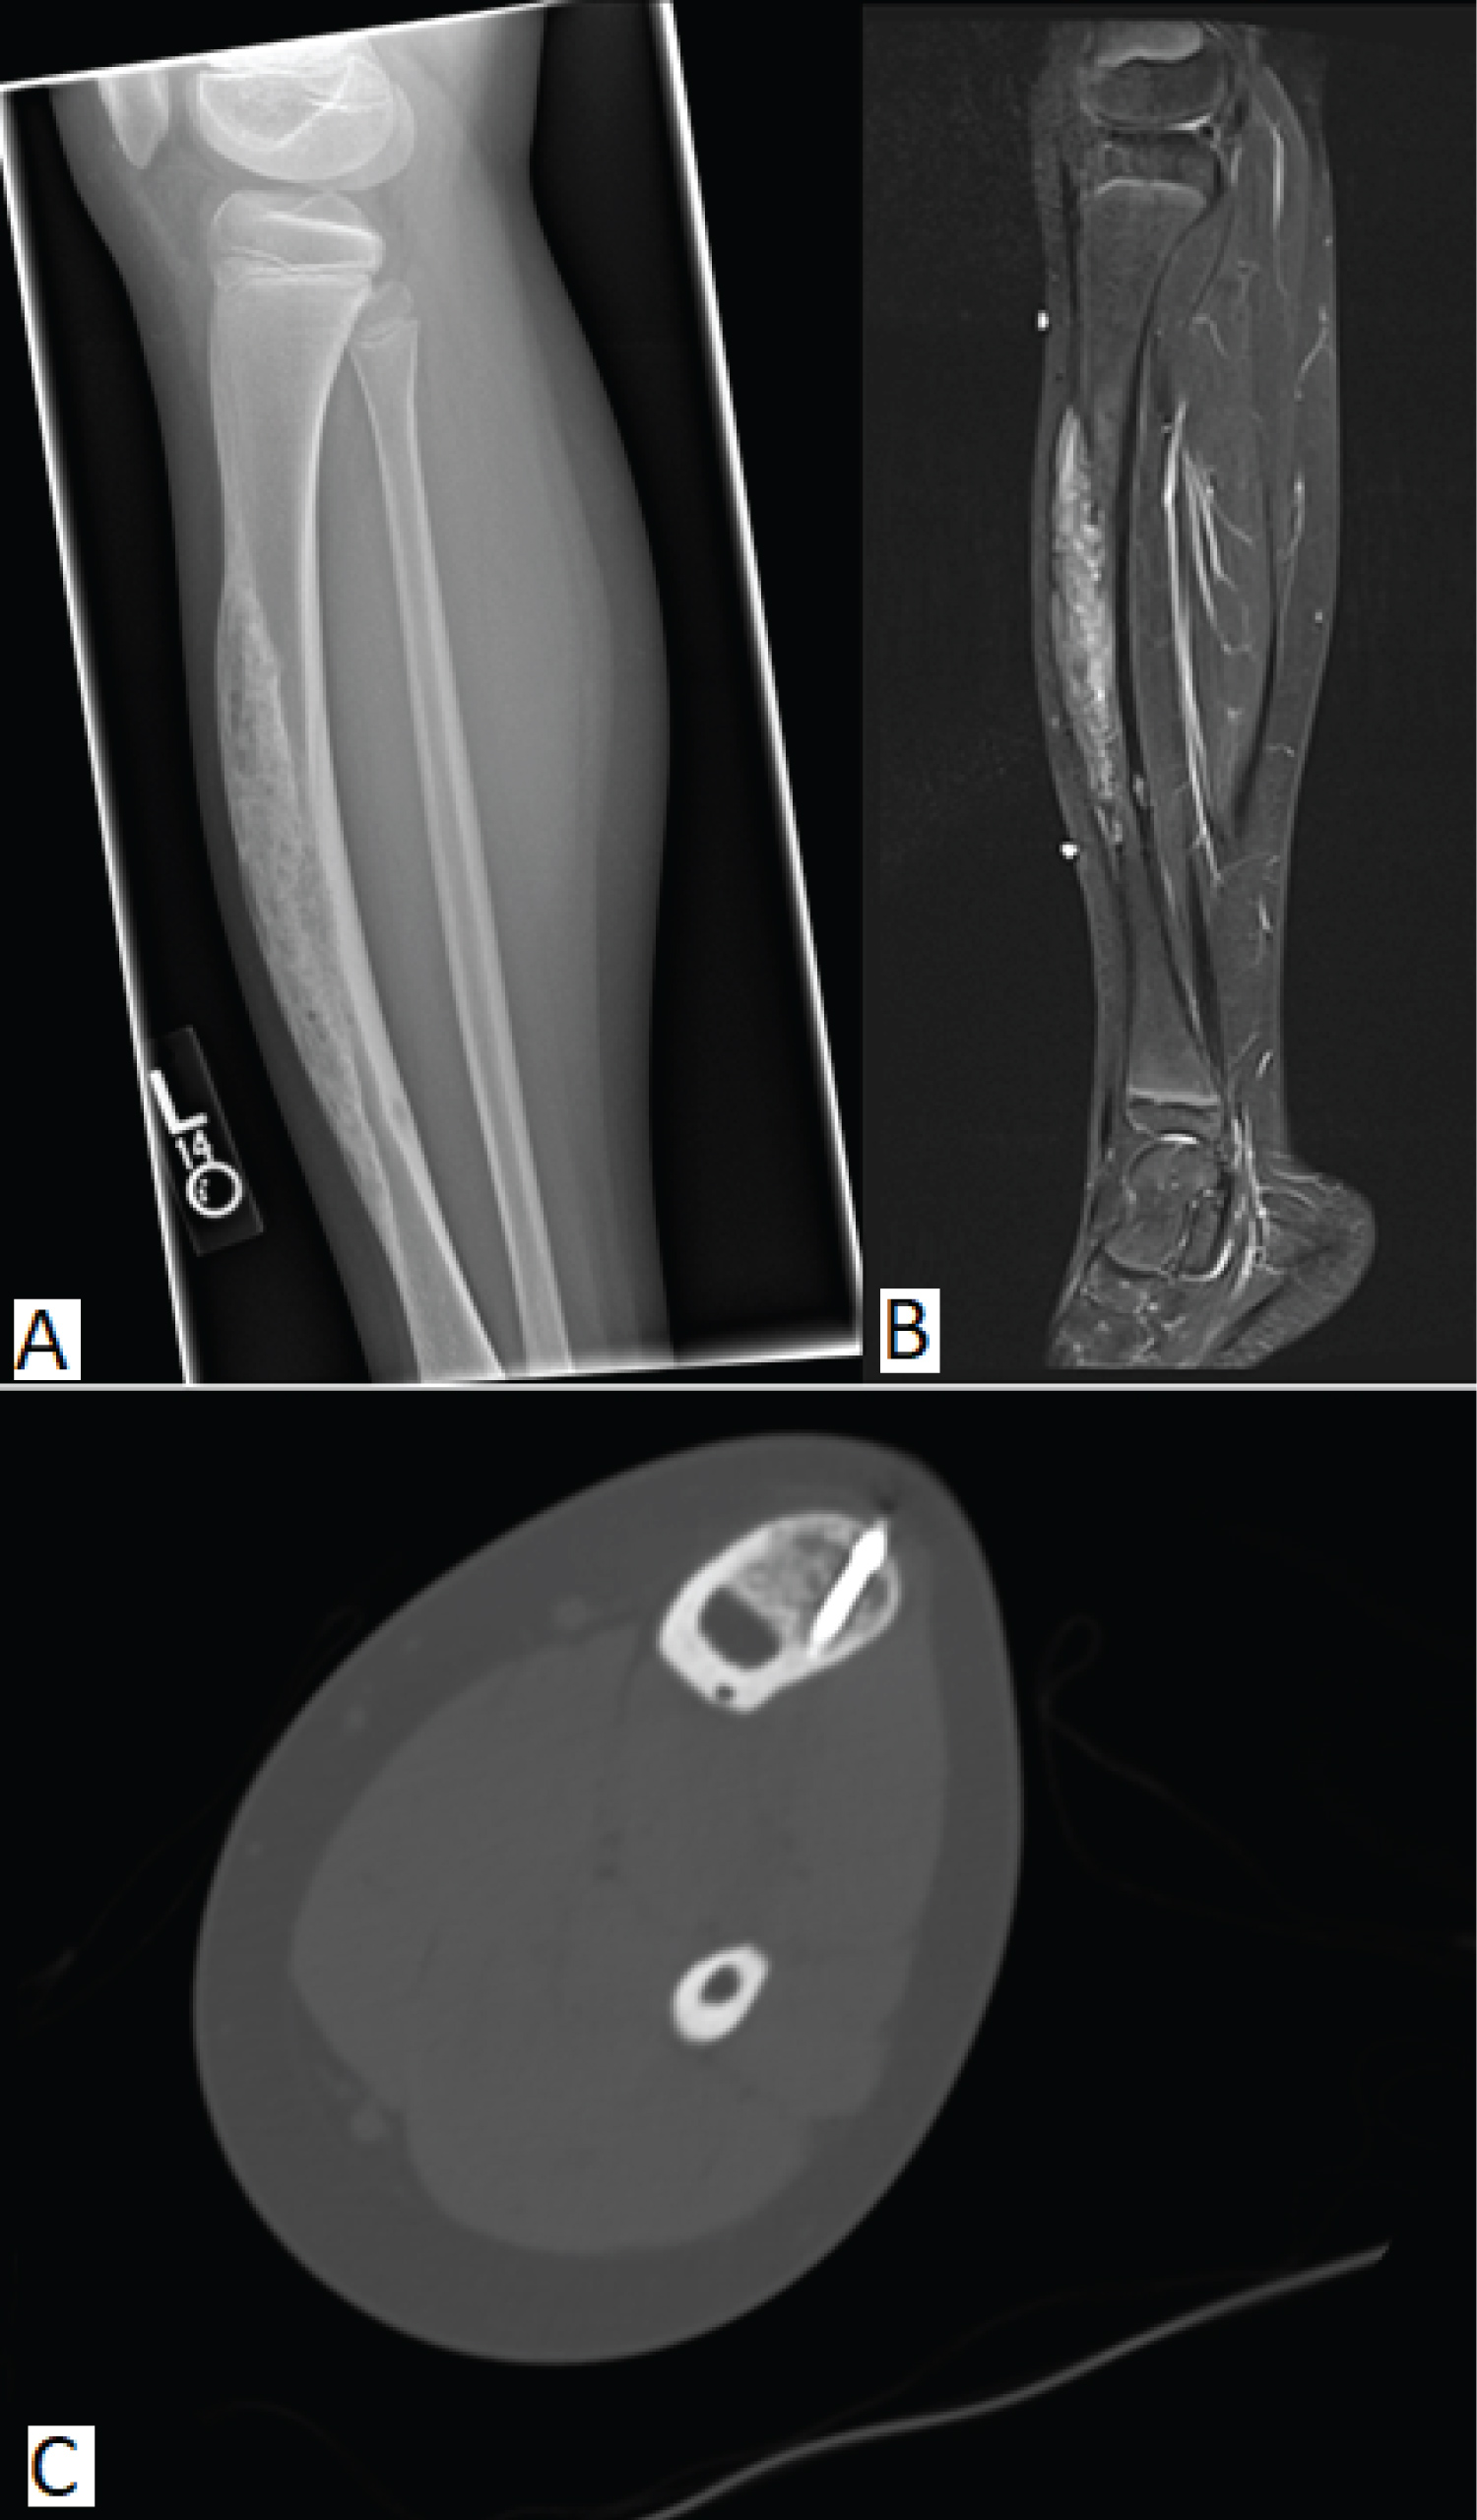

An 11-year-old male with a past medical history of pes planus, metabolic syndrome and left lower extremity pain and swelling presented to our institution with a 2-year history of abnormal gait. The patient and his mother reported a bump in the anterior leg that had been present for more than a year but became tender to palpation at 6 months prior to presenting to clinic. Physical exam noted a 2 cm growth on the left mid-anterior tibia with mild internal rotation of the left lower extremity. Plain radiographs (Figure 1A) found focal moderate cortical expansion in the anterior aspect of the mid tibia with cortical irregularity and sclerosis with superimposed numerous small foci of bony lucency. This finding was confirmed with CT and MRI (Figure 1B and Figure 1C) to reveal an infiltrative, 16.6 cm expansile lesion with its epicenter in the mid-tibial diaphysis and was associated tibial bowing anteriorly and poorly defined proximal and distal margins. The mass was described as a mixed lytic and blastic tibial diaphyseal lesion. CT-Guided bone biopsy showed a fibro-osseous lesion of thickened woven bone and lamellar bony trabeculae embedded in loose fibrous stroma composed of bland spindle cells. Within the spindle cell stroma scattered clusters and cords of epithelioid cells resembling vessels and epithelial clusters were identified. (Figure 2A and Figure 2B) Immunostains for AE1/AE3 (Figure 3B) showed rare foci of positivity in the form of epithelial clusters; cytokeratin CAM 5.2 was negative (Figure 3A). Immunostains also showed scattered nests and chords of epithelial cells highlighted by 34BE12 and cytokeratin OSCAR. The tumor was treated by excision with wide margins. The patient was managed with allograft placement and reconstruction. A computed tomography scan of the chest, abdomen, and pelvis showed no signs of metastasis.

Figure 1: (A) Expansile, heterogenous lesion arising from the anterior tibial cortex with lucent and sclerotic features. Posterior margins are partially obscured by sclerosis, but without periosteal reaction or soft tissue mass; (B) CT showing an infiltrative, 16.6 cm expansile lesion with its epicenter in the mid-tibial diaphysis with associated tibial bowing anteriorly and poorly defined proximal and distal margins; (C) STIR (short tau inversion recovery) revealing a lesion with heterogenous signal intensity with overall increased STIR signal. View Figure 1